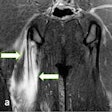

Dorsal rim impaction syndrome, also known as hypertrophic synovitis, is a type of carpal impingement syndrome that predominantly affects the trailing wrist in elite golfers, and dorsal impaction syndromes are also seen in athletes, notably gymnasts, weightlifters, and those who do excessive press ups, the authors continued. Plain x-ray and CT are usually normal as this condition, at least initially, is a capsular soft-tissue abnormality. Dorsal capsular thickening can be shown on ultrasound or MRI, but MRI is more reliable in documenting its extent as well as any concomitant injuries or bone marrow changes elsewhere in the wrist.

Plain x-ray can be diagnostic for its presence, but if negative because of bony overlap, CT or MRI can define the bossing. MRI should be performed routinely in elite golfers as this technique can also demonstrate associated bone marrow edema, fracture, soft-tissue edema, and/or tendon abnormality, the Leeds group recommended.

Finally, dorsal ganglion cysts of the wrist are the most common focal lesions in the hand and wrist in the general adult population, and are also common in elite golfers. On MRI, ganglia are typically fluid signal being low signal on T1-weighted images and high signal on T2-weighted images, but a high proteinaceous content or hemorrhage can result in lesions appearing isointense or hyperintense on T1-weighted images.

A narrow stalk connecting the ganglion to the joint is often visualized. The sonographic findings mirror MRI, and typically a hypoechoic fluid-filled mass is seen with a narrow stalk extending toward the joint. An elongated neck can cause the ganglion to surface at distance from the joint and appear at an apparent atypical location, they concluded.